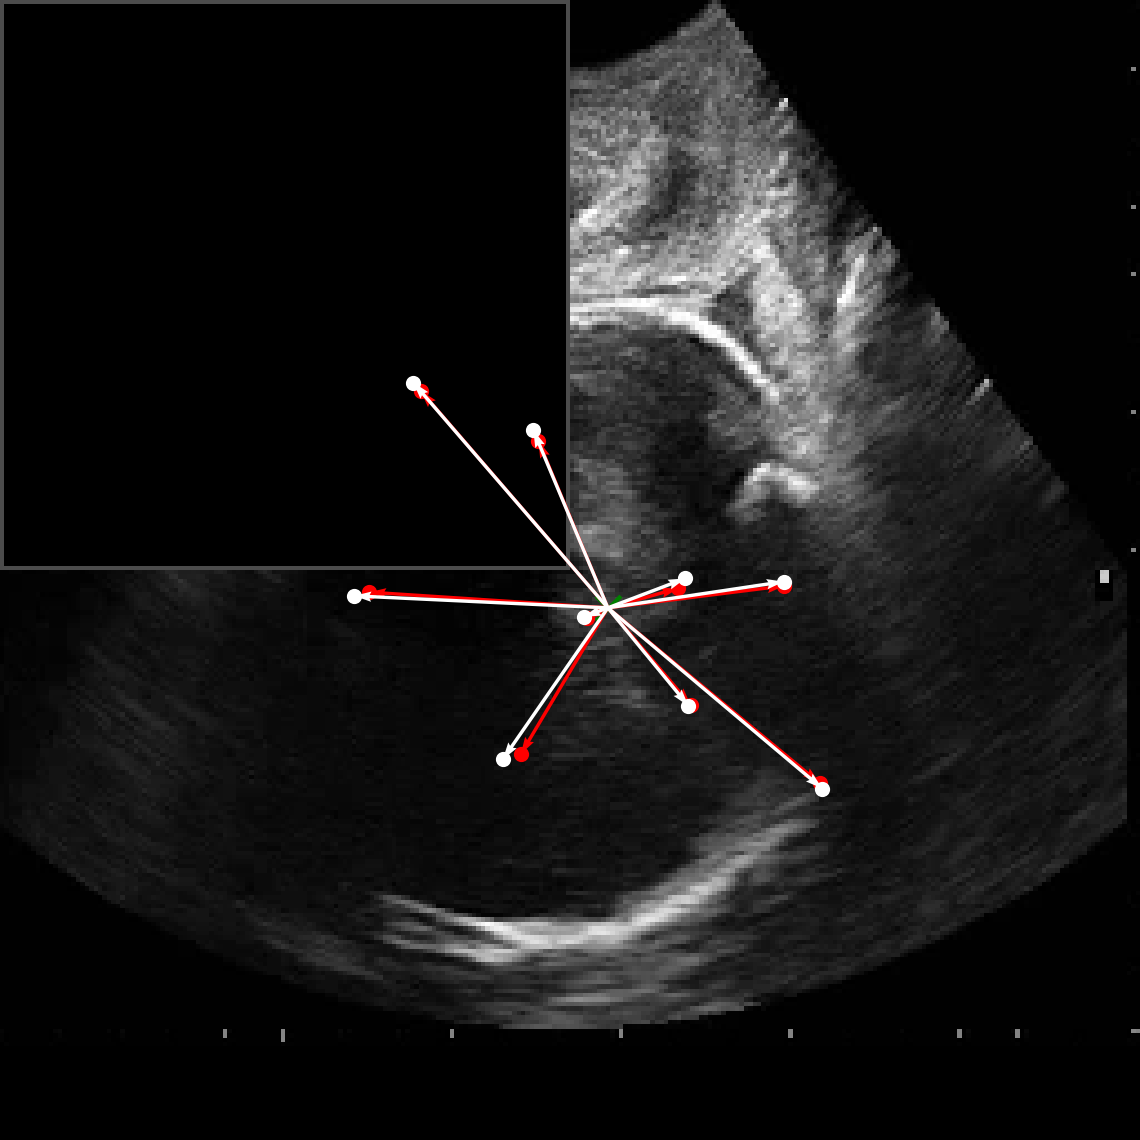

In practical clinical settings, medical images are often incomplete or degraded due to occlusions, artifacts, or limited fields-of-view. Therefore, a reliable segmentation model must be robust to missing spatial context and capable of inferring anatomical structures from partially observed inputs. To evaluate this critical property, we conducted a masking experiment using the FH-PS-AoP dataset. In this experiment, we systematically removed one quadrant from the input image, top-left, top-right, bottom-left, or bottom-right, and evaluated the performance of DAUNet compared to the baseline UNet.

Figure 7 presents a comprehensive visual comparison of the predicted offset maps and segmentation masks under each masking condition. The first column shows the original (unmasked) input along with its corresponding predictions, while subsequent columns depict the results for each of the masked quadrants.

DAUNet demonstrates markedly higher resilience to missing context compared to UNet. Its predicted offset maps remain dense and structured, with vectors that preserve anatomical directionality even when significant regions of the input are absent. This behavior reflects DAUNet’s ability to infer context from the remaining visual cues. In contrast, UNet exhibits sparse or disoriented offsets in the masked scenarios, indicating reduced spatial awareness and compromised localization.

To better understand this phenomenon, we analyzed the receptive fields of both models. For a representative pixel, we visualized its corresponding receptive area contributing to the output. In UNet, the receptive field is fixed and grid-constrained (refer to second row of Figure 7), making it sensitive to occlusions. On the other hand, DAUNet leverages deformable convolutions to dynamically adjust its receptive field based on the visible content. This adaptability is evident in the red and white arrows in the fourth column of Figure 7, where DAUNet modifies its offset patterns to account for the masked input.

The segmentation masks in third and fourth rows of Figure 7, further substantiate these findings. DAUNet consistently produces anatomically plausible segmentations of both the fetal head (green) and pubic symphysis (red), with minimal degradation even under 25% missing input. The output contours remain smooth, accurate, and well-aligned with ground truth boundaries. In contrast, UNet’s performance deteriorates noticeably, with fragmented or distorted segmentations, especially around the fetal head, as indicated by white arrows in the figure.

These results highlight the efficacy of DAUNet’s architectural innovations. The combination of deformable convolution and SimAM attention allows the model to effectively reason over the visible context and compensate for spatial omissions. This robustness to incomplete inputs makes DAUNet well-suited for deployment in real-world medical environments, where noise, occlusions, and partial data are common challenges.